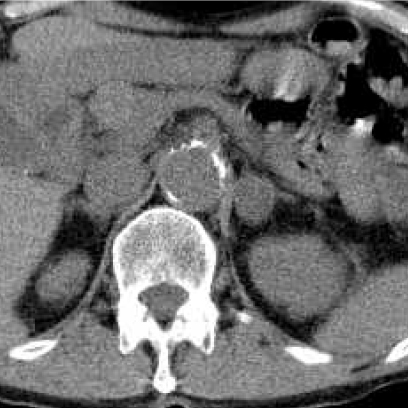

a. 123I-MIBG planar背面像

b. 単純CT

c. 123I-MIBG-SPECT/CT

図2 嚢胞変性した褐色細胞腫